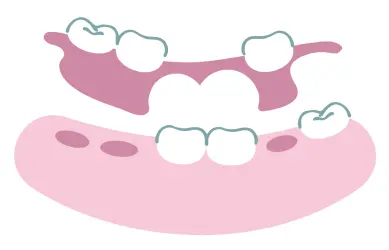

歯を失った場合の選択肢

ブリッジ

入れ歯

インプラント